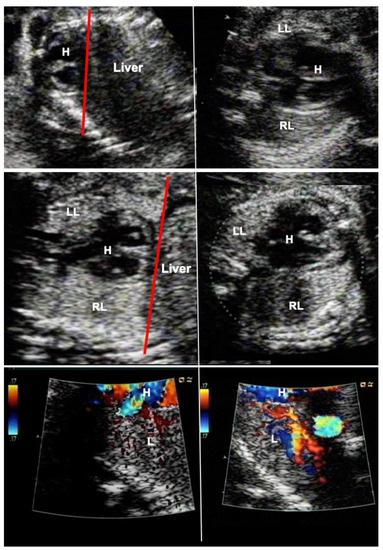

Figure 4.

Effect of FETO at 27 weeks of gestation in a fetus with severe pulmonary hypoplasia from anhydramnios after rupture of membranes at 15 weeks of gestation. Top left—severe compression of the fetus has resulted in a displacement of the heart–lung base to the level of the third to fourth rib (red line). Top right—there is pseudocardiomegaly and at the level of the four-chamber-view, the left lung (LL) can hardly be seen. Middle left—after one week of FETO, the lung has regained volume such that the heart–lung base now lies at the level of the 7th–8th rib (red line). Middle right—as a result, the four-chamber-view has normalized, and the left lung can easily be seen. (RR—right lung). Bottom left—color Doppler imaging at a low Nyquist limit (17 cm/sec) demonstrates barely any color flow signals within the lungs one day after FETO. Bottom right—on the third day of FETO, color flow signals are clearly present in the fetal lung, heralding a better prognosis. As soon as fetal pulmonary vasodilatation can be provoked by diagnostic materno–fetal hyperoxygenation, the fetus is scheduled for fetoscopic balloon removal, delivery, and postnatal treatment.